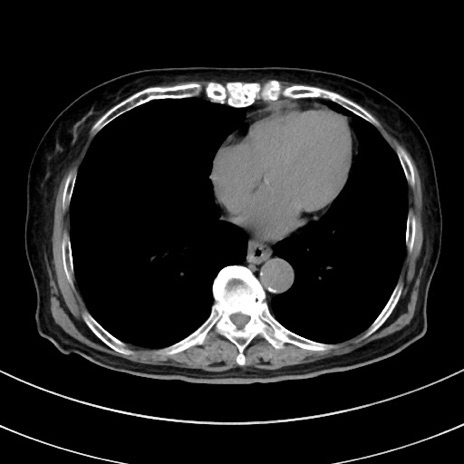

症例33(横断像)

【症例】70歳代 女性

【主訴】心窩部痛

【現病歴】延髄病変の精査・加療にて神経内科入院中。本日より心窩部痛あり。

【身体所見】右下腹部を中心に圧痛と反跳痛あり。

【データ】WBC 10900、CRP 0.02